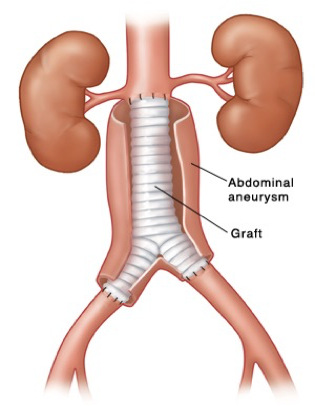

What does this refer to

Open surgical repair vs. endovascular

Open repair

Low or average risk of operative complications

Direct visualization

Open Repair Aortic Aneurysm